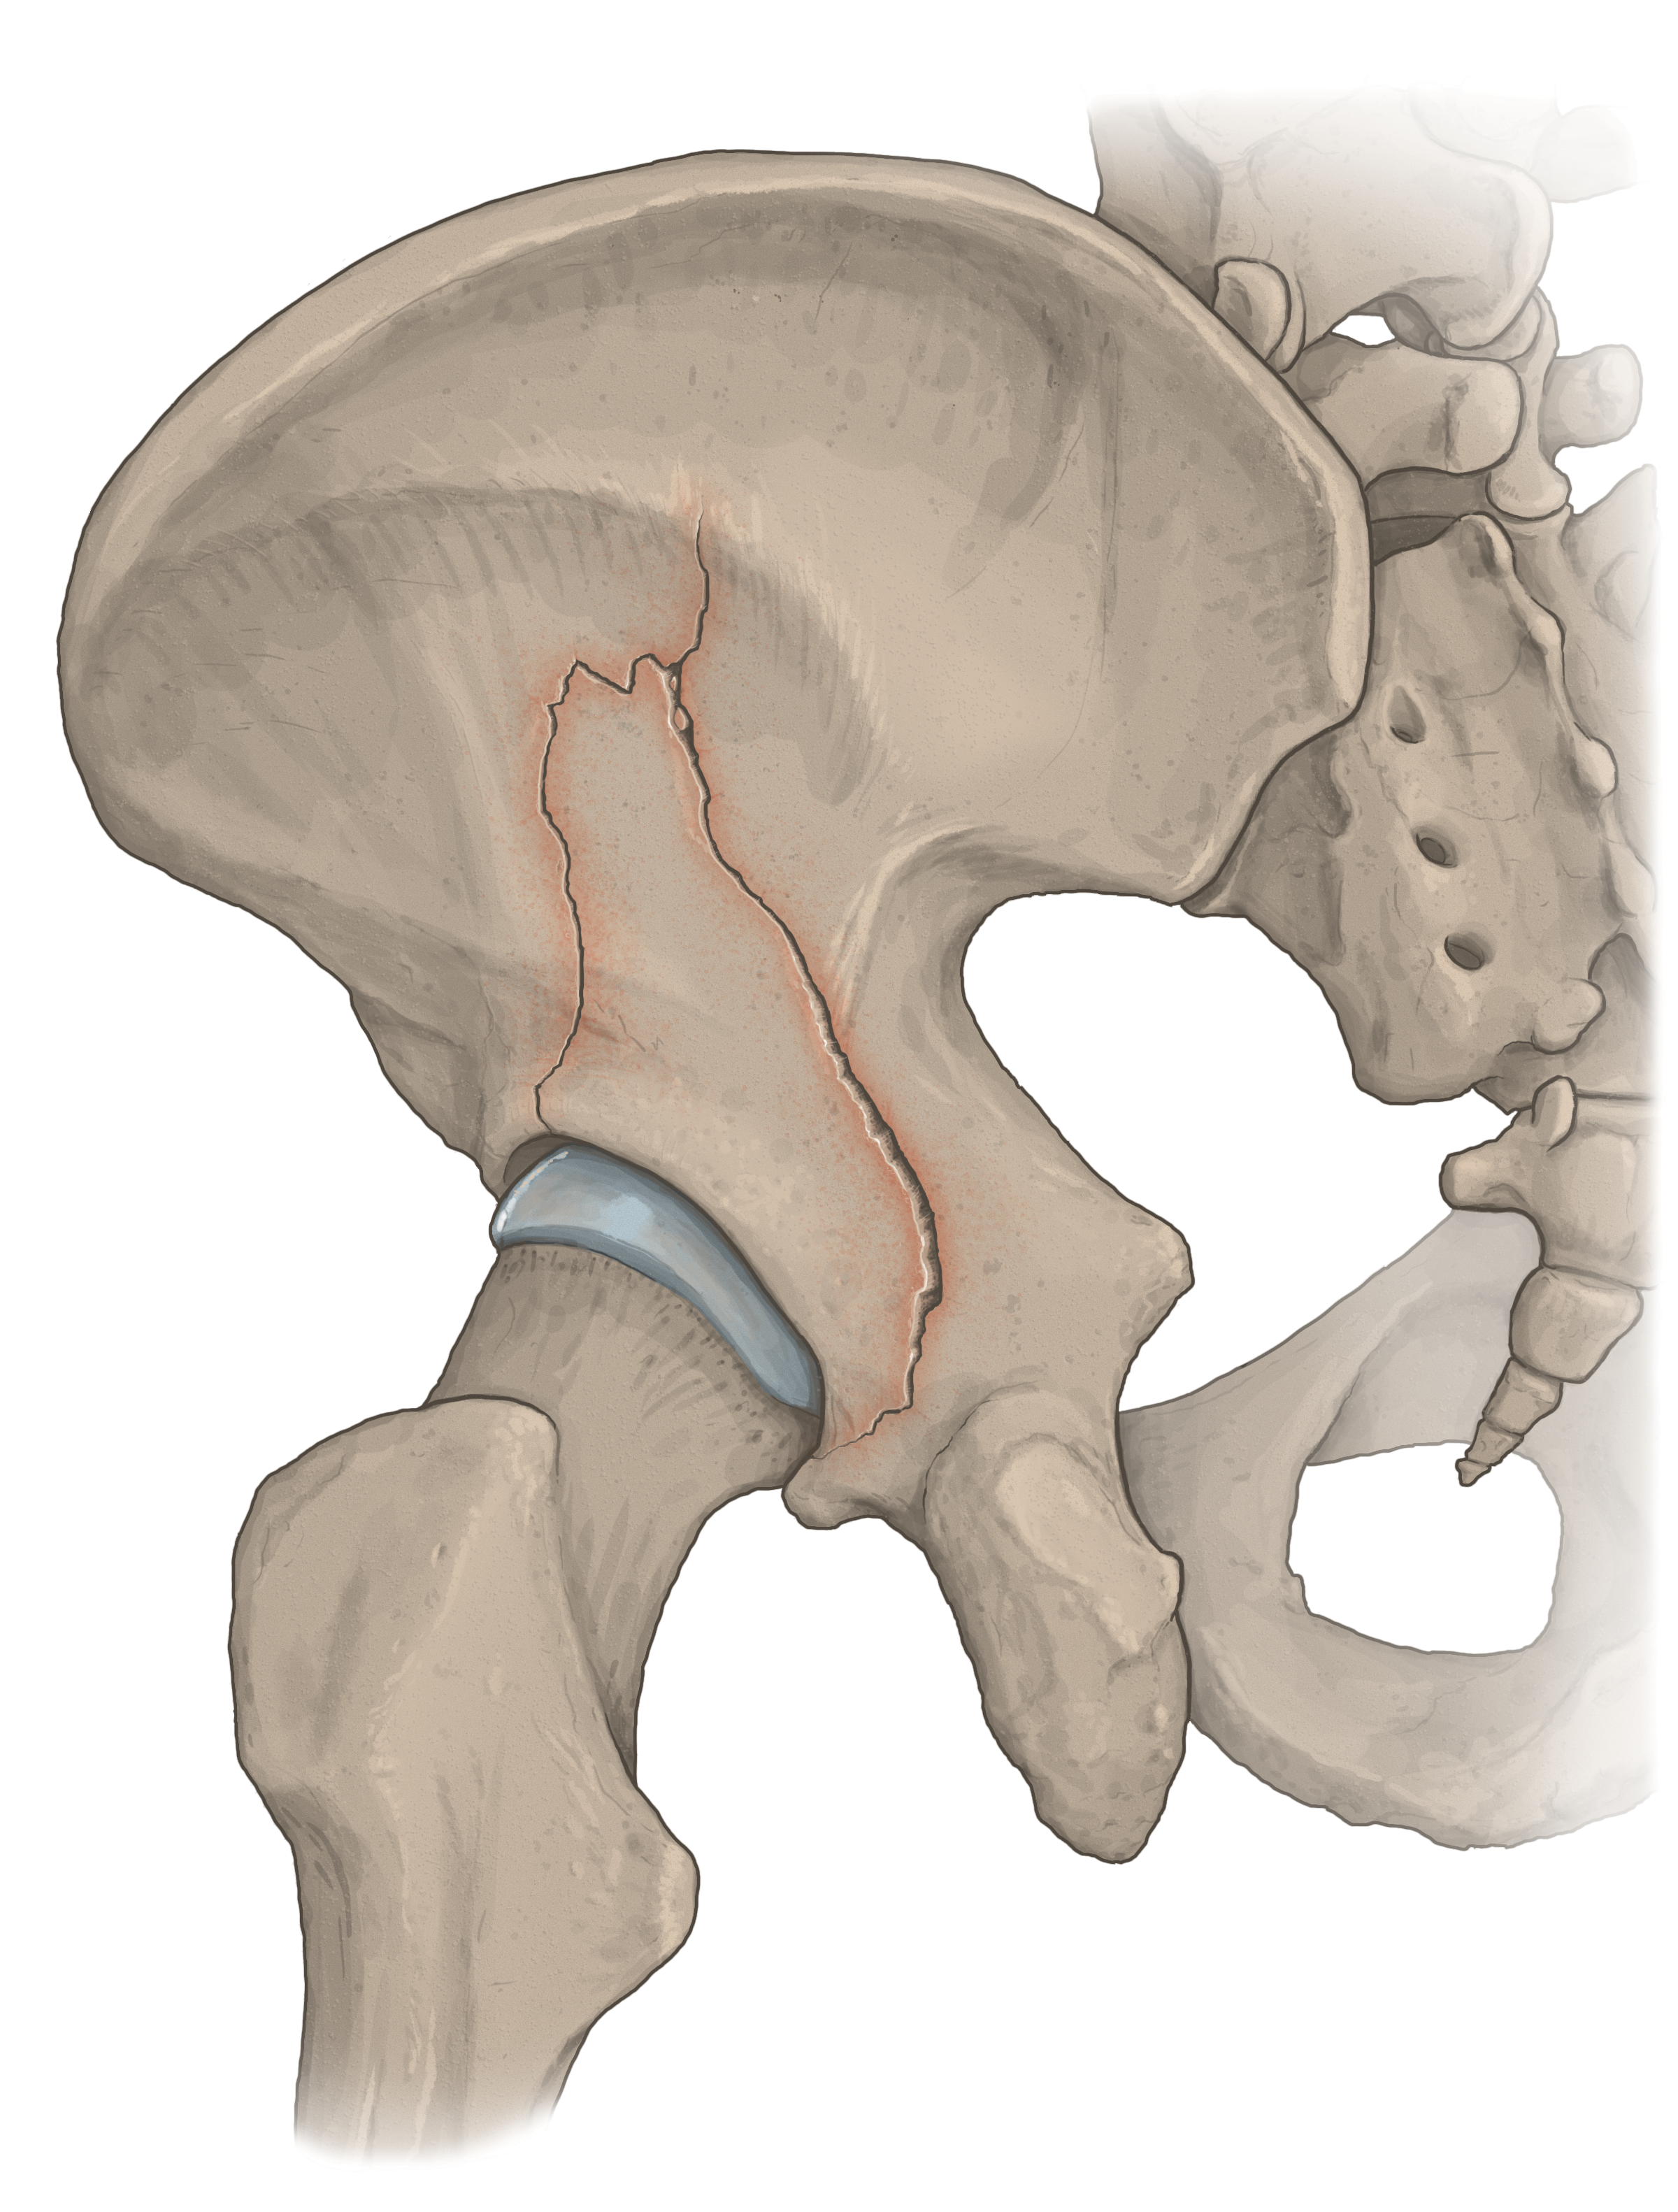

Medical Illustration

All images are works made for hire and are the exclusive property of the client. These are shown as sample purposes of my work only. For licensable work, please see my Illustration Services page.

Contract freelancer for many others, some examples of my work below.